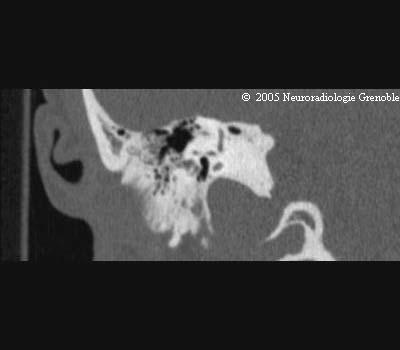

Radioanatomie TDM du rocher normal

Trou déchiré postérieur

Canal semi-circulaire supérieur

Vestibule

Canal semi-circulaire externe